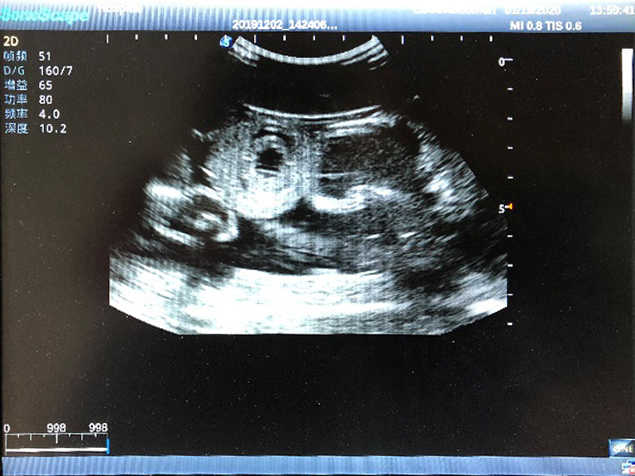

1)  Ideal for trainings like ultrasound-guided abdominocentesis with visible ascites flowing out, ultrasound-guided femoral artery & venous puncture

2)  High quality ultrasound image with clear structures like gallbladder, liver, intestines, arteries and veins etc.

3)  Compatible with all types of clinical ultrasound machines

5)  Normal & pathological ultrasound live and intestine models inside